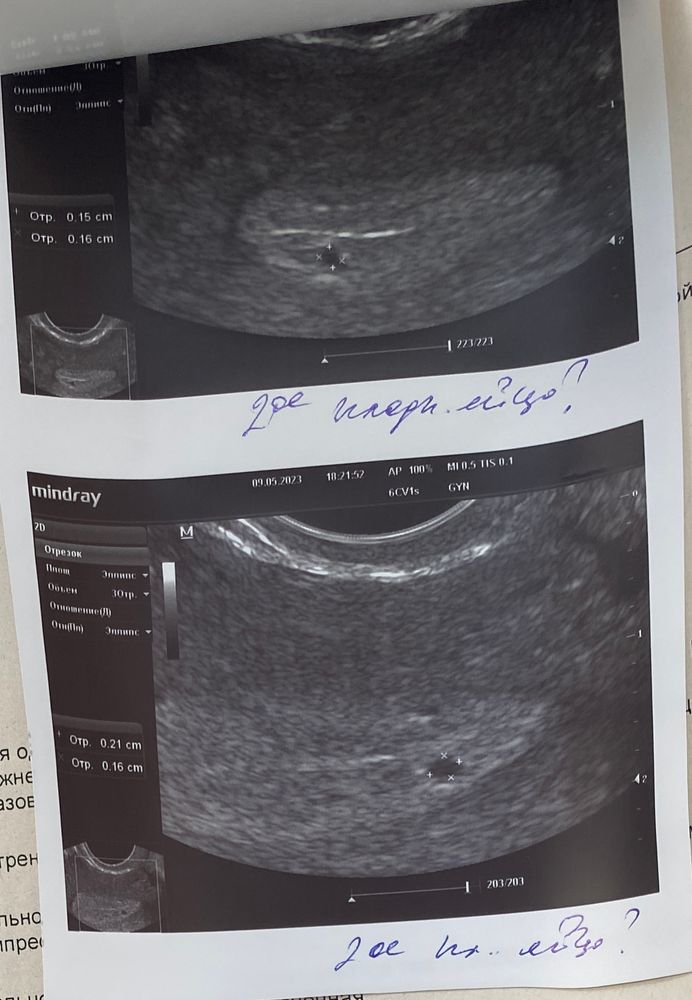

Подозрение на двойню

Доброе утро, акушерская 5 неделя и 4 дня . Была на узи, сказали что в двух яичниках есть желтое тело, значит овуляции было две. В матке нашли плотное яйцо и еще одно что то, но меньшего размера. Какова вероятность что это второе плотное яйцо? У кого нибудь может были похожие случаи

у меня было такое, что на первом узи ставили два плодных яйца, оказалось что второе это железы эндометрия.Так же было одно крупнее другого. Правда срок у меня меньше был и овуляция у меня была в одном яичнике